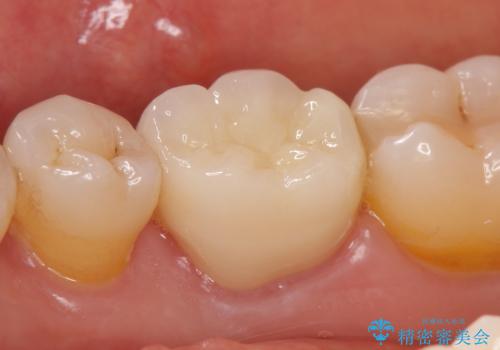

今回用いたオールセラミッククラウンはジルコニアフレームという白い素材の上にセラミックを盛っているため、審美性が非常に高いのが特徴です。

また、ジルコニアは人工ダイヤモンドの材料にも使われているほど高い強度を持っており、そのためオールセラミッククラウンは審美性だけでなく、奥歯やブリッジの補綴も可能とするクラウンです。